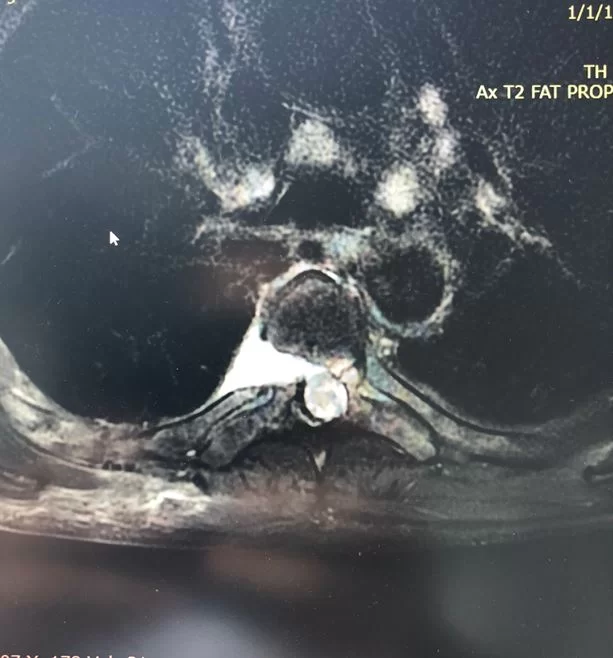

Ο απεικονιστικός έλεγχος ανέδειξε δύο επασβεστωμένες θωρακικές δισκοκήλες στο ύψος Θ6/7 και Θ7/8.

Διενεργήθη διαθωρακική προσπέλαση και μικροχειρουργική αφαίρεση και των δύο δισκοκηλών.

Οι θωρακικές δισκοκήλες, ειδικά όταν είναι επασβεστωμένες, αποτελούν χειρουργική πρόκληση, μια και η δισκοκήλη είναι σε άμεση επαφή με το νωτιαίο μυελό, ενώ στην προσπέλαση είναι σημαντικό να διαφυλαχθούν σημαντικές δομές όπως τα μεγάλα αγγεία του θώρακα, ο πνέυμονας κλπ.